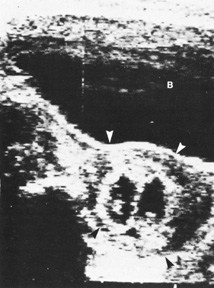

Diagnostic ultrasound is widely used in the assessment of pregnancy and the fetus. Although clinical benefits of routine ultrasonography during pregnancy have not been established, approximately 70% of pregnancies in the United States undergo ultrasound evaluation.30 Because most instruments used in diagnostic ultrasonography produce energies no greater than 10 to 20 mW cm2 (safety defined as less than 100 mW cm2), ultrasound is considered generally safe. No harmful biologic effects on instrument operators, pregnant women, fetuses, or other patients have been found. Infants exposed in utero have shown no significant differences in birth weight or length, childhood growth, cognitive function, acoustic or visual ability, or rates of neurologic deficits (see Fig. 6).

Fig. 6. A: First-trimester twin intrauterine gestations. Ultrasound examination of the pregnant uterus (arrowheads) shows the “owl eyes” characteristic of early twin pregnancies. B: Maternal urinary bladder. (Courtesy of Alfred B. Kurtz, MD)

Fetal number (Fig. 6)